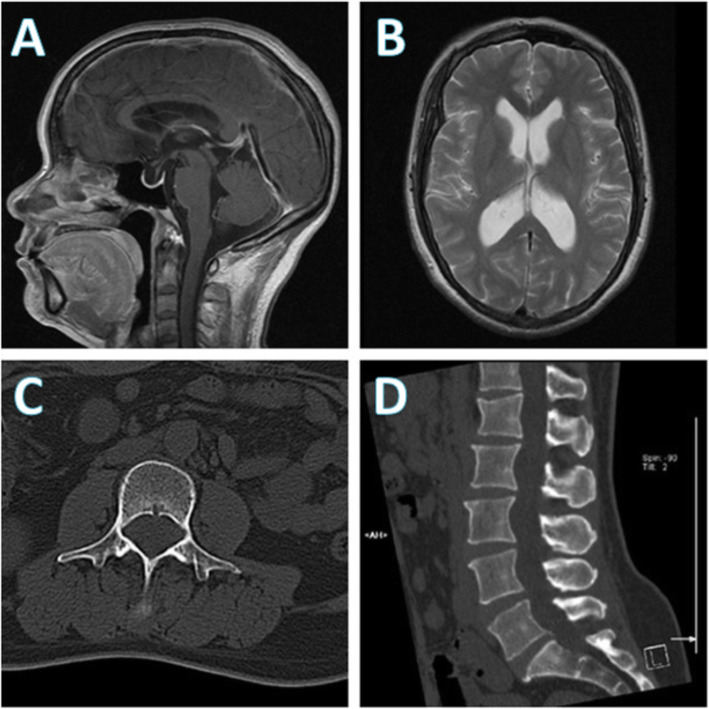

From pmc.ncbi.nlm.nih.gov

Intracranial hypertension due to spinal cord tumor misdiagnosed as What Level Is Lumbar Puncture Done  A lumbar puncture is an invasive test designed to access the subarachnoid space in the lower spinal canal. Opening pressure is measured with a manometer; In lumbar puncture (lp), a needle is inserted into the lumbar subarachnoid space to collect cerebrospinal fluid (csf) for laboratory testing, to measure csf pressure, and sometimes. The brain and spinal cord are covered by. What Level Is Lumbar Puncture Done.

Frontotemporal brain sagging syndrome Craniospinal hypovolemia What Level Is Lumbar Puncture Done  A lumbar puncture (lp) or spinal tap may be done to diagnose or treat a condition. Opening pressure is measured with a manometer; In lumbar puncture (lp), a needle is inserted into the lumbar subarachnoid space to collect cerebrospinal fluid (csf) for laboratory testing, to measure csf pressure, and sometimes. A lumbar puncture (lp), which is also called a spinal. What Level Is Lumbar Puncture Done.

Intracranial hypertension due to spinal cord tumor misdiagnosed as What Level Is Lumbar Puncture Done  What can i expect after a lumbar puncture (spinal tap)? The brain and spinal cord are covered by three. A lumbar puncture (lp), which is also called a spinal tap, is a common neurological test that's done to examine the cerebrospinal fluid (csf)—the protective fluid that surrounds. The puncture site is then covered with a sterile adhesive strip. 4 tubes. What Level Is Lumbar Puncture Done.